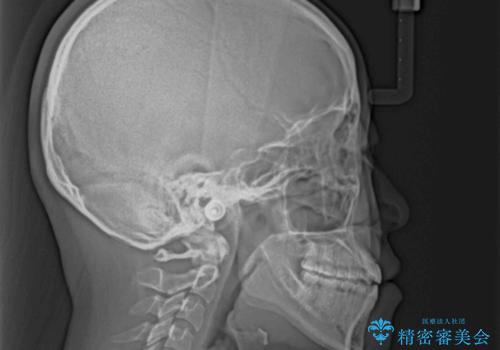

上顎骨を拡大したことで、下顎の歯列を上顎が受け入れられるようになりましたが、インビザラインでは咬み合わせを改善させることができなかったため、ワイヤー矯正にて仕上げることとしました。

ワイヤーを使用したものの、上下前歯のオープンバイトがなかなか改善されませんでしたが、患者希望により治療終了となりました。